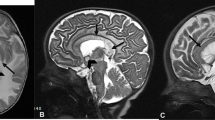

Impairment of protein homeostasis leading to proteotoxic stress and activation of the unfolded protein response (UPR) has been implicated in ASD [8]. Drivers of impaired protein quality are increased spontaneous modifications by glycation, oxidation, and nitration [9]. Glycation of proteins occurs by spontaneous reaction of proteins with glucose, reactive dicarbonyl metabolites, glyoxal, methylglyoxal (MG), and 3-deoxyglucosone (3-DG), and other saccharides and saccharide derivatives. Protein glycation adducts are classified as early stage glycation adducts—such as Nε-fructosyl-lysine (FL) residues formed by glycation of proteins by glucose—and late-stage adducts, advanced glycation endproducts (AGEs)—such as Nε-carboxymethyl-lysine (CML) and glucosepane (GSP) residues—formed by the degradation of FL residues, hydroimidazolones G-H1, MG-H1, and 3DG-H formed by the modification of arginine residues by glyoxal, MG and 3-DG, respectively, Nω-carboxymethylarginine (CMA)—also formed by the reaction of glyoxal with arginine residues, and methylglyoxal-derived lysine crosslink (MOLD). Protein oxidation occurs by the reaction of proteins with reactive oxygen species (ROS) and is increased in oxidative stress. Examples of protein oxidation adducts are dityrosine (DT), N-formylkynurenine (NFK), α-aminoadipic semialdehyde (AASA), and glutamic semialdehyde (GSA) residues. Oxidative stress has been implicated as a contributory factor in the development of ASD [10,11,12]. Increased oxidative damage associated with oxidative stress and neuroinflammation may be common features of ASD in children. Protein nitration occurs by the reaction of proteins with reactive nitrogen species such as peroxynitrite. The main adduct formed by protein nitration is 3-nitrotyrosine (3-NT) residues (Fig. 1). Increased protein damage by these mechanisms may lead to activation of the UPR to counter the proteotoxic threat and related inflammatory response [13, 14].

Protein glycation, oxidation, and nitration free adducts. Ionization status at physiological pH is shown. For related adduct residues of proteins, alpha-amino-NH3+ and terminal carboxylate –CO2− groups are moieties of as peptide bonds –NH–CO– with amino acid residues immediately before and after in the peptide backbone